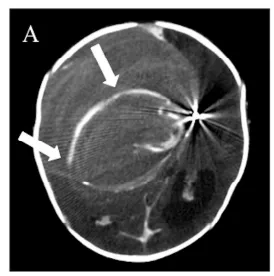

术后过程平稳:患儿清醒、反应好,自主呼吸恢复并顺利经口喂养。早期影像排除手术并发症,轻度脑积水缓解,遂拔除引流管并出院。

亨利术后24个月随访未见晚期并发症(图4)。在亨利4岁时随访,神经功能与认知发育均达满意水平。

图4